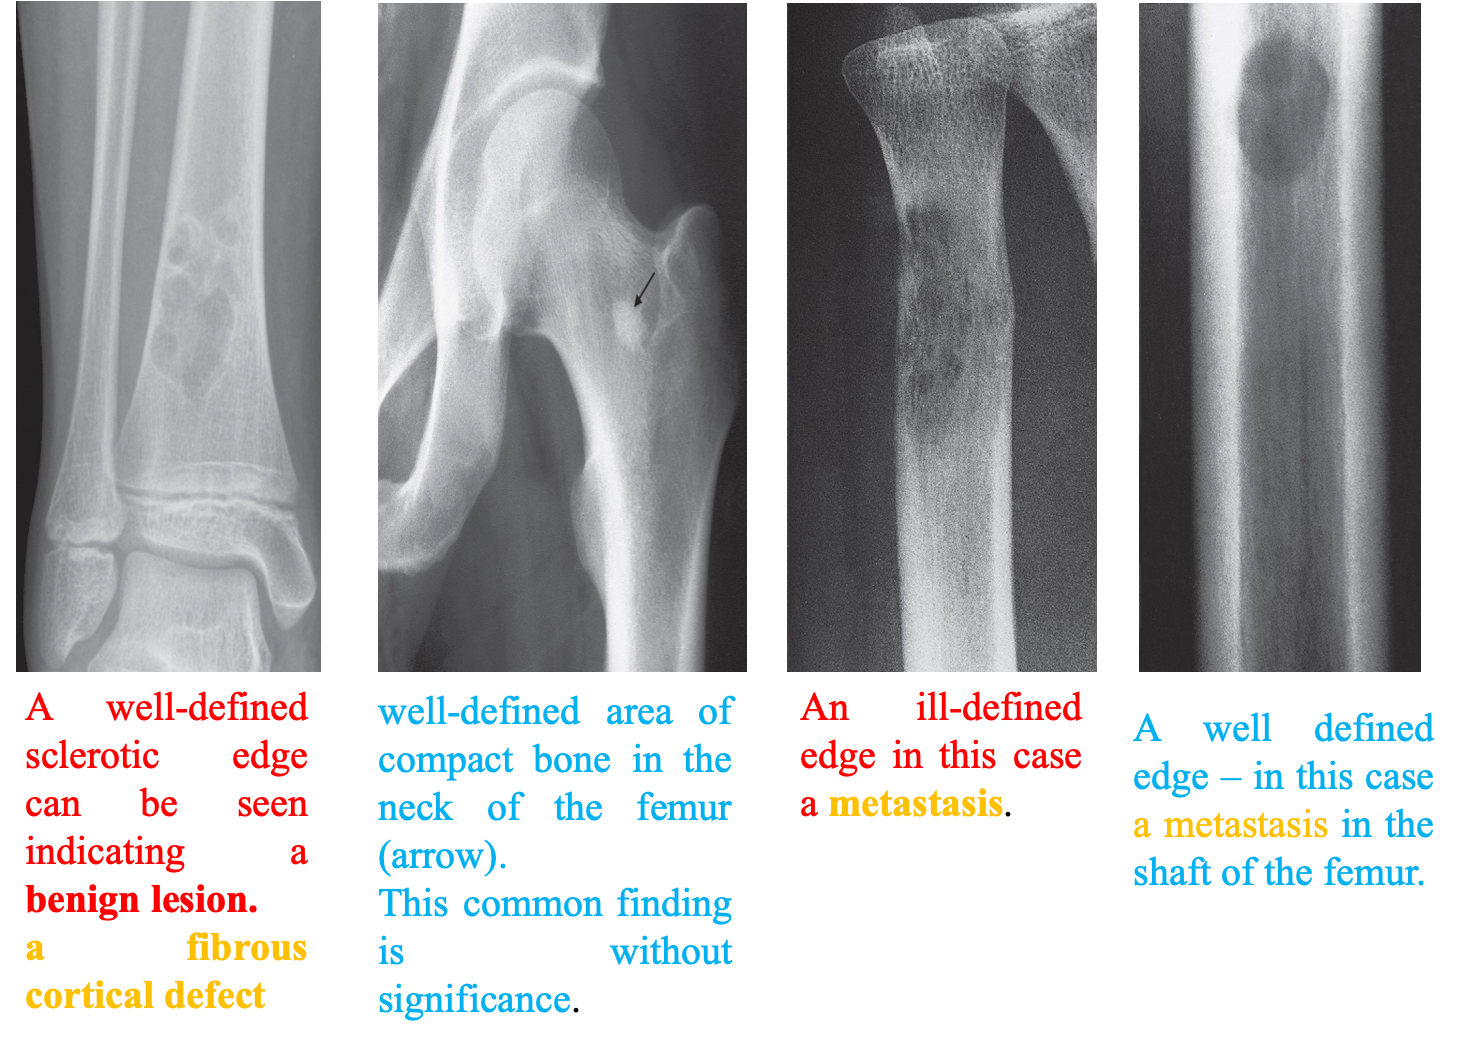

A. Well demarcated.

- A lesion with a well-defined sclerotic edge is almost certainly benign, e.g. a fibrous cortical defect or a bone island.

B. Wide zone of transition: between the normal and abnormal bone.

- A lytic area with an ill-defined edge is likely to be aggressive.

C. Lytic area with no sclerotic rim,

- which may be a benign or malignant leson. Metastases and myeloma are a frequent cause of this pattern.